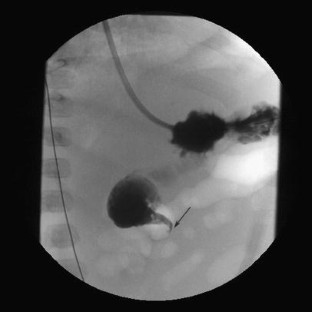

Enhanced CT perfusion cut-off sign in midgut volvulus

We present a case of malrotation with midgut volvulus in an infant in which we discovered a unique CT sign called the perfusion cut-off sign. We hope this case will help establish this crucial diagnosis in other cases.

Fig. 1